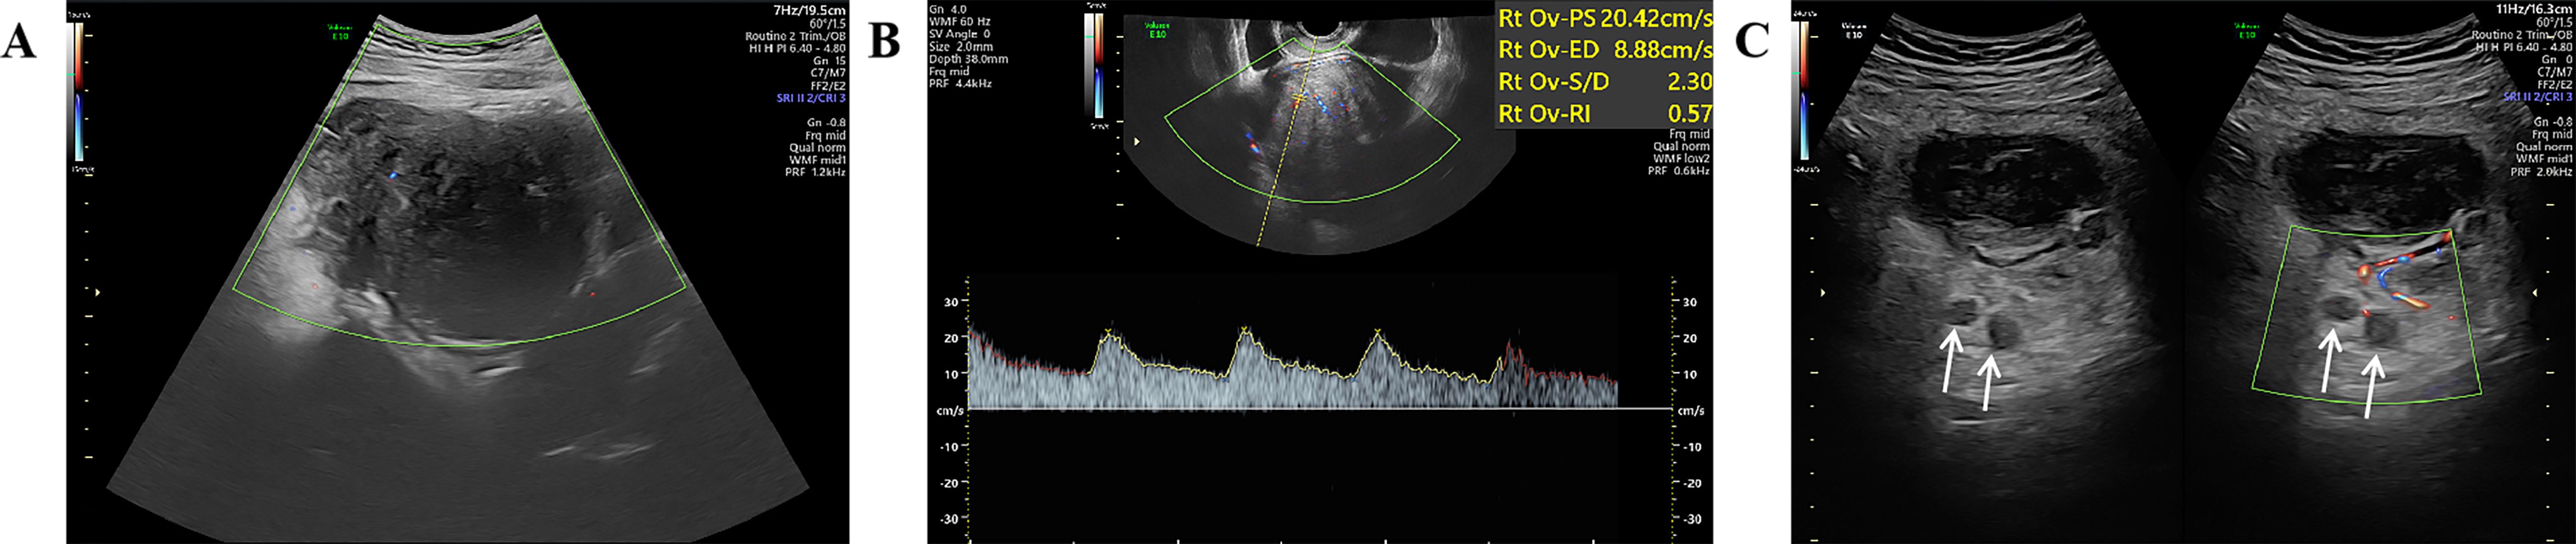

A 27-year-old woman came to the doctor because of intermittent pain in the lower abdomen for more than 1 month and fever 1 day ago. During this period, the symptoms were relieved after oral medication (details are unknown). A week ago, there was no obvious inducement for migratory abdominal pain, which transferred from the umbilicus to the right lower abdomen, and the pain worsened after changing the body position. Physical examination: obvious tenderness in the right lower abdomen, no rebound pain and muscle tension. A mass about 10 cm × 8 cm in size was palpable in the pelvic cavity, with unclear boundaries and inactive adhesions to the pelvic cavity. Blood routine examination: white blood cell count 13.1 (109/L)↑, neutrophil count 10.9 (109/L)↑, monocyte count 1.3 (109/L)↑, neutrophil ratio 82.7 (%)↑, lymphocyte ratio 8.7 (%)↓, acidophage ratio 0.0 (%)↓, high-sensitivity C-reactive protein 140.2 mg/L↑. Ultrasound examination: A hypoechoic mass with a size of about 11 cm × 8 cm ×10 cm was found in the pelvic cavity, The internal echo is uneven, with no obvious liquefied areas or calcification foci. The mass has a clear boundary and a relatively regular shape; CDFI: punctate blood flow signals were seen in it, PW: PS: 20.4 cm/s, S/D: 2.3, RI: 0.57. Two circular hypoechoic nodules were found in the right abdominal cavity, the larger one was about 13 mm × 13 mm (Figure 1). Ultrasound suggests: hypoechoic mass in pelvic cavity, considering neoplastic lesions, the source cannot be defined; Enlarged lymph nodes in the right abdominal cavity. CT examination revealed a slightly higher density mass in the pelvic cavity, about 10 cm × 9 cm in size, with a CT value of about 25HU. The edge was under smooth and the lesion enhancement was uneven. The local enhancement of the upper edge was obvious, and the overall enhancement was mild. The branch vessels of the superior mesenteric artery passed through it, the space around the lesion was blurred, and multiple enlarged lymph node shadows were seen. The mass is located above the bladder, anterior and superior to the uterus and closely adherent to it, with indistinct boundaries from the right adnexal region broussonetia papyrifera. The sigmoid colon is displaced cephalad and posteriorly (Figures 2, 3). Between the mass and the bladder, compressed small bowel loops can be visualized. CT suggested: pelvic space-occupying lesions, adjacent multiple lymph nodes enlarged, and neoplastic lesions were considered. The patient underwent surgical treatment. During the operation, a huge mass was found in the ileocecal part, about 15 cm × 14 cm × 13 cm in size. The tumor was necrotic, and pus moss attached to the surface. The lesion involved part of the ascending colon and terminal ileum, and about 200ml of purulent exudate was seen in the abdominal cavity. Finally, the mass was completely removed, and part of the intestinal tube and omentum were removed. Pathological examination: naked eyes: a mass can be seen on the serosal surface of one side of the intestinal tube, which is closely connected with the intestinal tube, It has a size of 12 cm × 12 cm × 10 cm. The capsule of the mass is complete and smooth. The cut surface is gray and white. It is a solid mass with medium texture. The cut surface is fish - like and seems to have a mucus feeling, and bleeding and edema can be seen on the surrounding intestinal wall. Microscopically, the tumor boundary is unclear, infiltrating into the muscle layer of intestinal mucosa. The tumor cells are bundled and arranged in a woven way, and some areas are wavy. Collagen fibers can be seen to alternate, and some lymphocytes and neutrophils can be seen infiltrating. The morphology of the tumor cells is mild, slender spindle - shaped. The nucleus chromatin of the tumor cells is sparse or vacuolar, and some small nucleoli can be seen. Immunohistochemical results: β - Catenin (nuclear +), CD117 (–), CD34 (–), DOG - 1 (–), Desmin (partial +), Ki - 67 (+, ~ 5%), PHH3 (showing mitosis), S - 100 (–), SDHB (+), SMA (–), SOX - 10 (–) (Figure 4). Pathological diagnosis: Spindle cell tumor in the “giant tumor of ileocecal region”, combined with acute pyogenic inflammation of omentum. Combined with morphological and immunohistochemical results, it is consistent with IAF. After operation, the patient was transferred to ICU ward for symptomatic treatment such as anti - infection, nutritional support and fluid rehydration. On the 10th day after operation, pelvic CT re - examination showed that there were a small amount of exudative changes in the fat space in the operative area, thickening of mesangium, omentum and fascia, and a little localized gas accumulation. The patient was discharged on the 11th postoperative day. During the 3rd month of follow - up, pelvic CT showed that intra - abdominal pneumatosis and exudation in the operative area had been absorbed, and no recurrent imaging findings were found.

Figure 2

Figure 2. Pelvic CT axial view shows: (A plain scan, B enhanced arterial phase, C enhanced venous phase) A slightly hyperdense mass is seen in the pelvic cavity with ill-defined margins, blurred surrounding spaces, and heterogeneous enhancement, with more obvious enhancement in the upper part of the lesion.